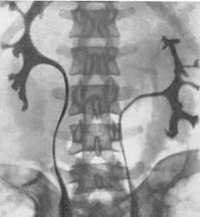

Внутривенная урография. Подковообразная левая почка.

Подковообразная почка встречается чаще других и представляет собой увеличение одного из полюсов почки, в 90% – нижнего. Нередко меняется и положение подковообразной почки, которая может быть смещена медиально или даже на противоположную сторону. Подковообразная почка видна при любом виде исследования – внутривенной урографии , УЗИ, КТ, МРТ почек или сцинтиграфии.